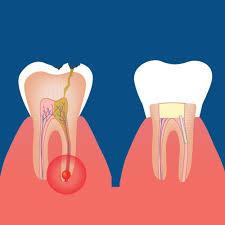

Root Canal Treatment